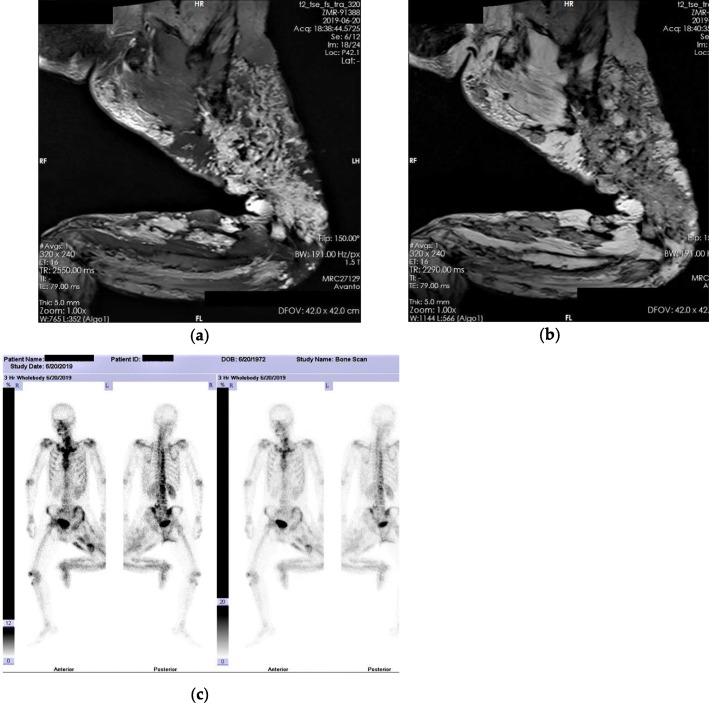

After hospitalization, the patient’s lateral thigh wound began to show signs of necrosis on the 3rd day. Lower extremity digital subtraction angiography (DSA) showed vascular distribution and blood supply of the diseased limb (Fig. 3a-b). No arteriovenous fistulas were found during DSA. On the fifth day, bacterial culture from the wound showed a gram-positive bacterial infection. On the seventh day, an amputation was performed at the fracture site to the proximal of the infected necrotic foci. Owing to the high amputation plane, a tourniquet could not be used. Due to extensive vascular malformations and soft tissue ossification, bleeding during surgery was excessive and difficult to control by conventional electrocoagulation and ligation. Extensive ossification impeded the progress of the surgery. The intraoperative blood transfusion was 17 units. The patient was transferred to the intensive care unit (ICU) for advanced life support. Ossification specimens provided histopathologic evidence of HO (Fig. 3c-d). Normal trabecular bone formation and bone structure construction were detected. The patient was discharged on the 33rd day after hospitalization, and a postoperative X-ray was performed (Fig. 4). In order to maintain hemoglobin stability, the patient was transfused 55 units of blood during hospitalization. On follow-up at 2 months, the amputation wound healed well.

Fig. 3.

Necrosis and surgical outcome. a-b Lower extremity digital subtraction angiography shows vascular distribution. c-d Pathological specimens of ossification shows trabecular bone formation and bone structure construction. c magnification × 100 and d magnification × 40 (Hematoxylin & Eosin staining). The blue arrows show osteocytes

Fig. 4.

Postoperative X-ray showed fracture site after amputation